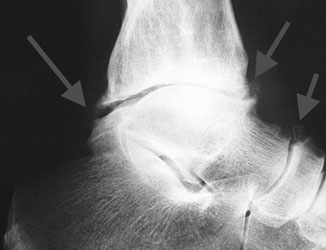

- Рентгенография. Самый важный диагностический параметр. Позволяет увидеть характерные неанатомические разрастания, имеющие вид шипов, крючков.

рентген голеностопного сустава. - КТ. Метод, позволяющий понять строение остеофитов. Также он помогает обнаружить патологию на начальной стадии, когда рентгена может быть недостаточно для постановки диагноза.

- Дегенеративно-дистрофические остеофиты развиваются в результате дистрофического процесса в одном суставе или во всем суставном аппарате. На рентгенограмме такой остеофит выглядит как скопления птичьих клювов вокруг суставов. Остеофиты этого типа ограничивают подвижность позвоночника.

Костные разрастания образуются в крупных суставах – при артрозе в коленном или тазобедренном суставе, локтевом или плечевом. Их обнаруживают в суставах кистей и стоп (так называемая «пяточная шпора») при рентгенологическом исследовании. На снимках они выглядят как небольшие костные отклонения по краям или имеют вид мелких включений на поверхности поврежденного сустава. На более поздних стадиях остеофиты напоминают дорожкообразные отростки.